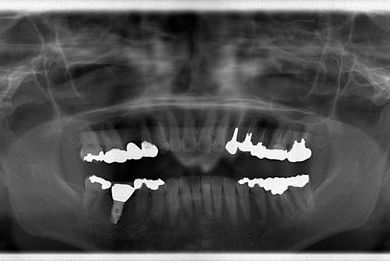

| 性別/年齢 | 女性 / 46歳 | ||||||||||||||||||||||||||||||||

| 主訴 | 歯ぐきがただれてる。歯が少しうずく。 | ||||||||||||||||||||||||||||||||

| 治療方針 | インプラント治療にて、機能的・審美的回復を行う。 | ||||||||||||||||||||||||||||||||

| 治療内容 | インプラント1本(GBR)、ハイブリッドセラミック1本 | ||||||||||||||||||||||||||||||||